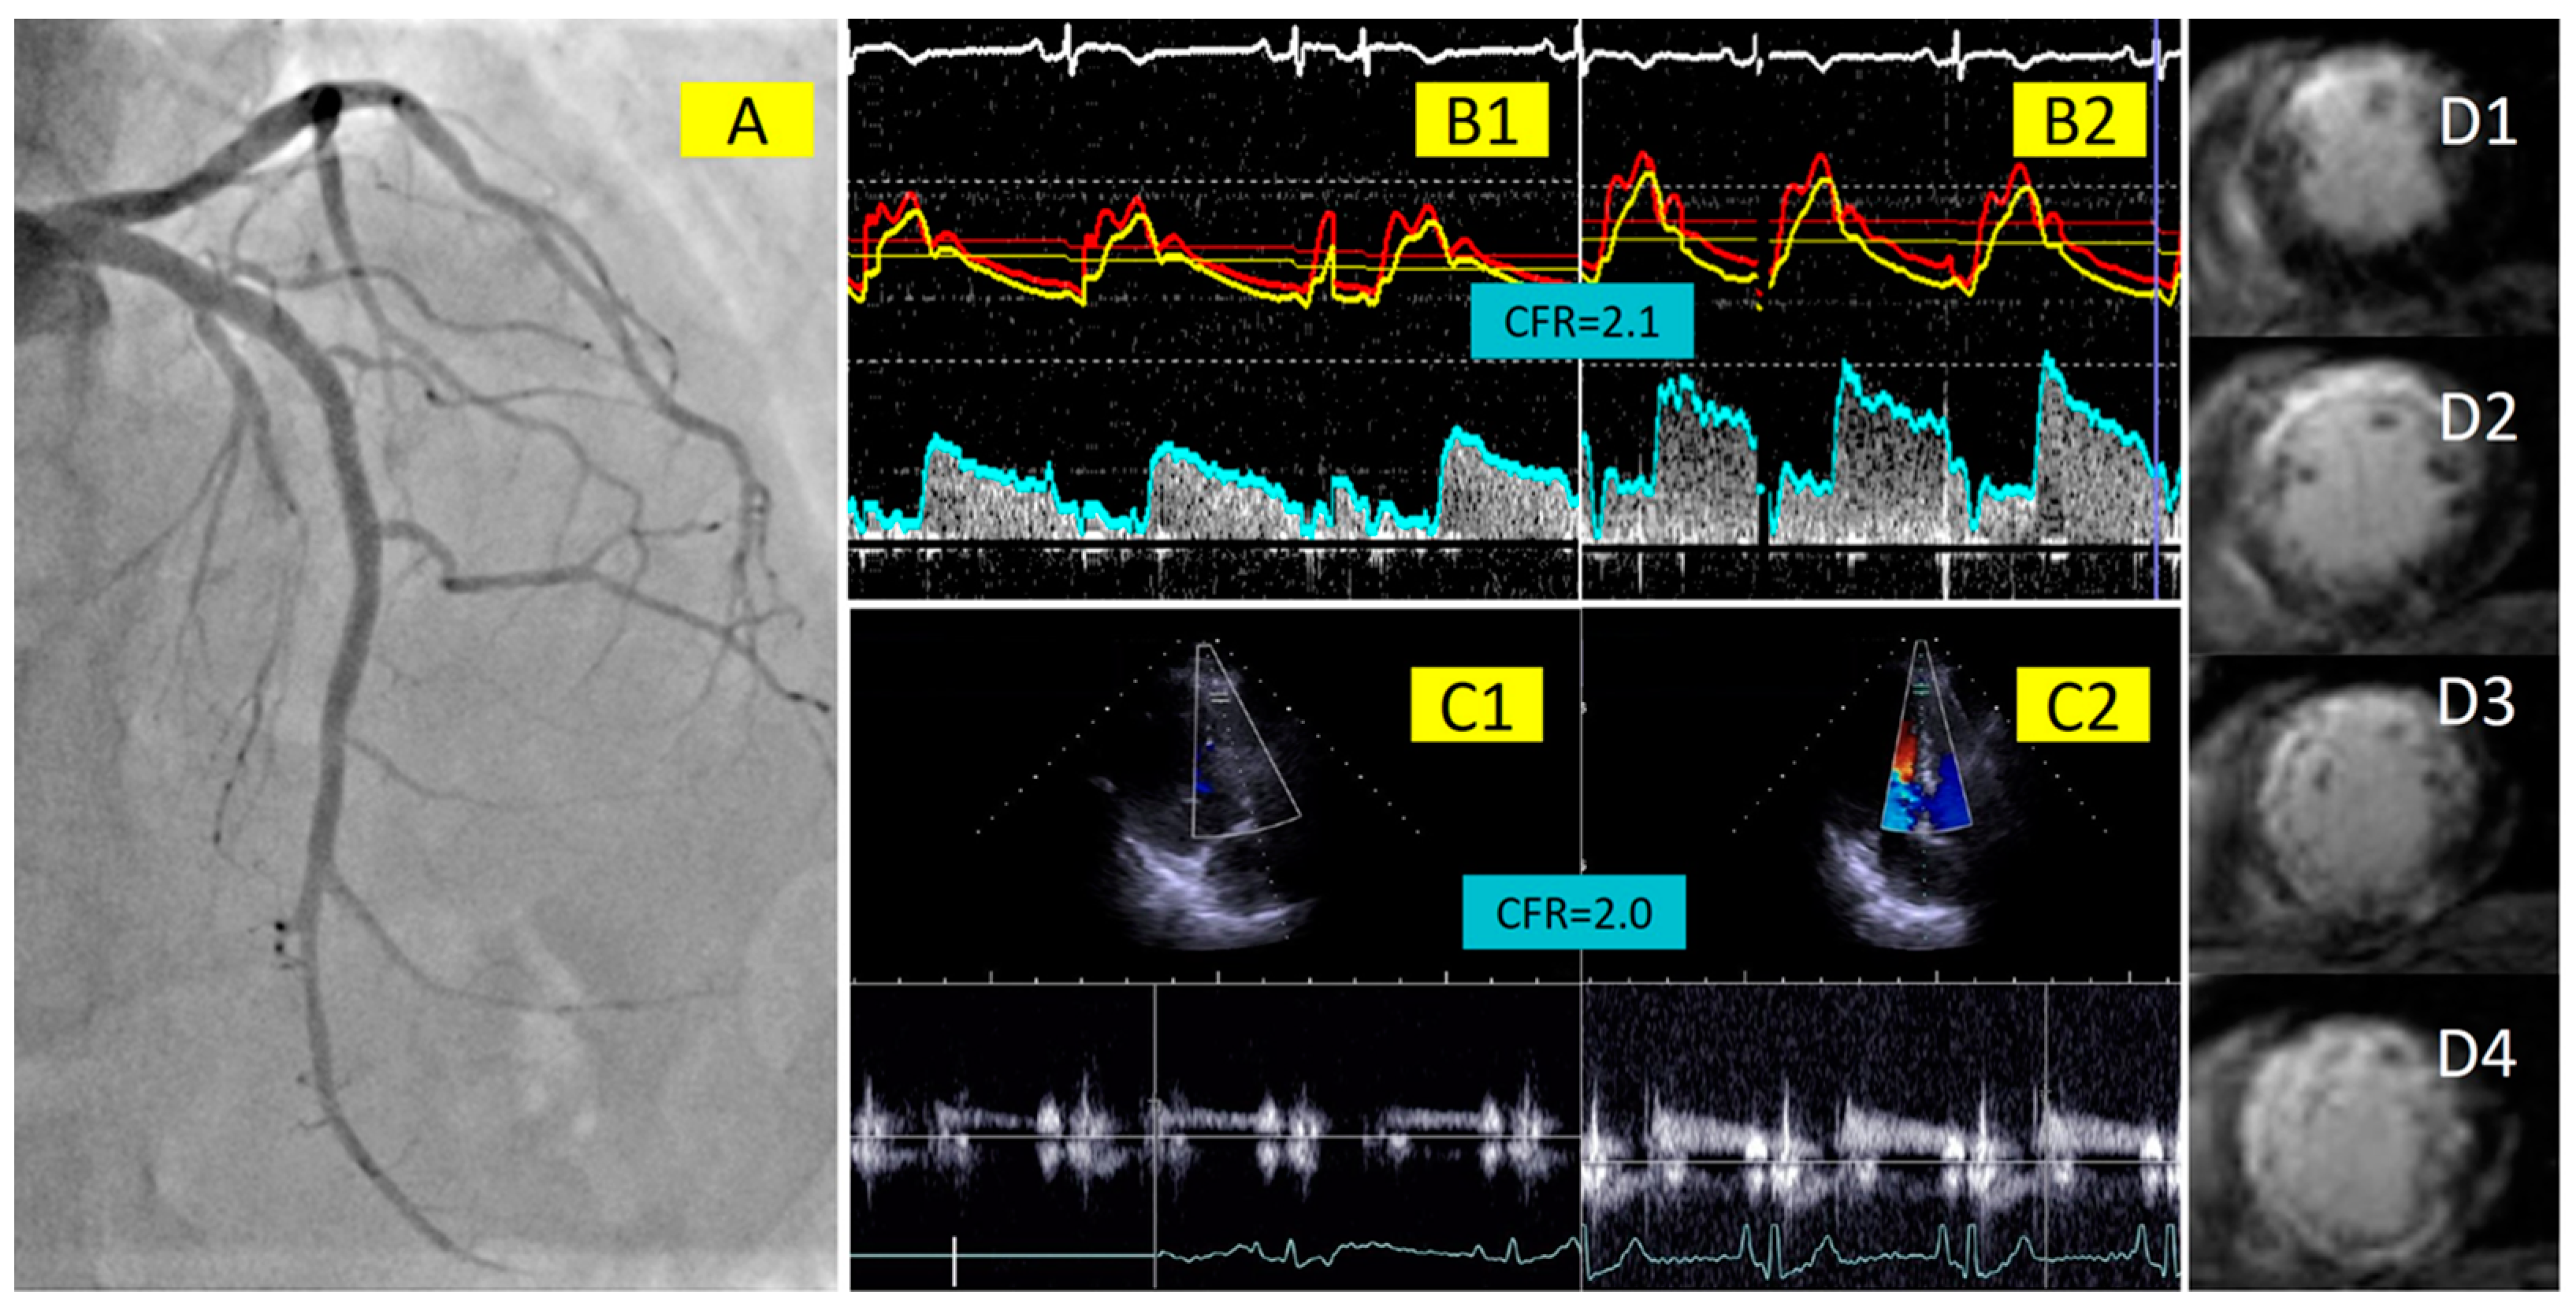

2.2. Invasive Measurements of Coronary Physiology Indices with Doppler Wire

2.3. Coronary Flow Velocity Measurement with Transthoracic Doppler Echocardiography

2.4. Cardiac Magnetic Resonance Imaging

3.2. Correlation between Invasive and Non-Invasive CFR